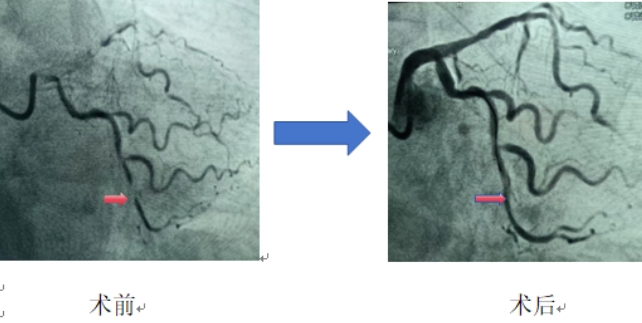

35岁的李先生,长期吸烟,突发胸痛1小时来海慈医疗北院区急诊科就诊,心电图检查发现急性下壁心肌梗死,病情危急!北院区立即启动导管室,心血管内科(含CCU、老年科)主任范广慈为患者紧急实施冠状动脉造影,显示患者左回旋支中段完全闭塞,开通闭塞冠脉后,综合患者年龄、病变部位的血管直径、血栓负荷情况及IVUS(血管内超声成像检查)结果,在对病变充分预处理后,对患者病变部位进行了药物球囊扩张处理,取得了满意的效果。目前患者病情恢复良好,定期随访中。